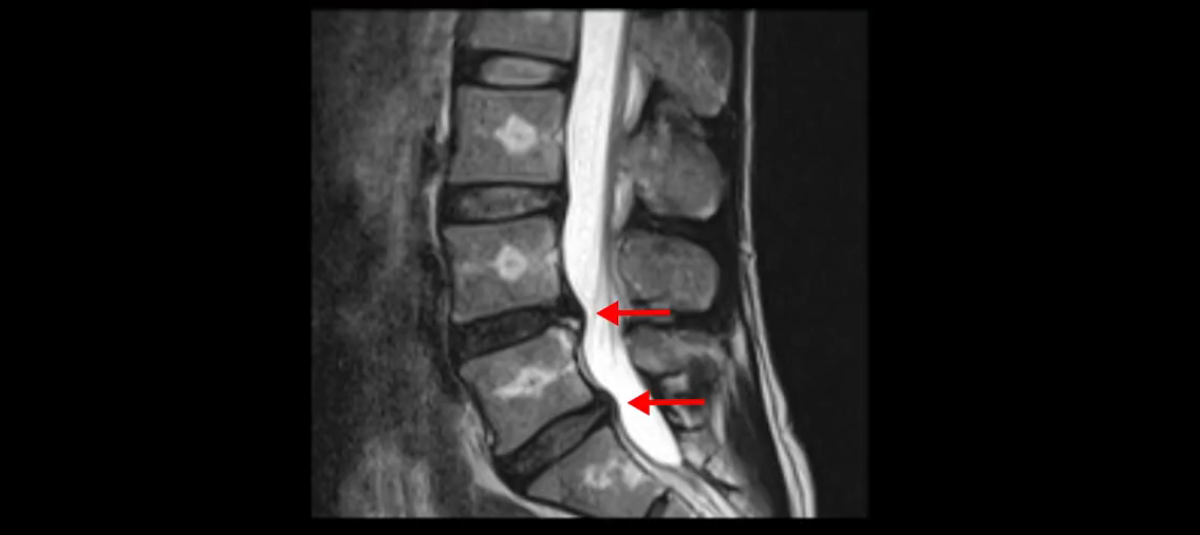

이분 MRI를 보시면 두 마디의 퇴행성디스크가 있습니다. 그리고 디스크가 조금씩 밀려 나와 있고요. 그런데 디스크 탈출 정도는 두 마디 다 심하지 않습니다. 4번 5번에는 디스크 탈출이 약간 있고,

척추관협착도 약간 진행이 되고 있고요.

5번 1번은 디스크 탈출이 가운데 쪽으로 살짝 있습니다.

중요한 것은 이 정도 경미한 탈출과 협착으로는 양쪽 다리가 저리고 아플 수가 없습니다.

그리고 만약에 이 디스크가 급성으로 찢어진 것이라면 아주 심한 디스크성 통증이 있겠죠. 기침이나 재채기를 하면 심하게 아프고 허리를 조금만 구부려도 아주 날카로운 통증들이 생길 겁니다. 그런데 이분은 이런 증상이 전혀 아닙니다. 디스크의 돌출 정도와 협착이 전혀 심하지 않기 때문에 이분이 가지고 계신 양쪽 다리 저림, 특히 이분은 누워있을 때도 양쪽 다리가 저리다고 하는데, 디스크 때문에 그런 증상은 생길 수가 없습니다. 또 이 디스크는 오래된 디스크, 이미 찢어진 섬유륜이 아문 디스크이고, 그러니까 이분은 기침이나 재채기를 못하는 증상이 없는 거죠. 그 다음에 허리를 구부릴 때 뻐근한 증상은 있지만 아주 날카로운 통증은 없습니다.

이분 MRI를 보시면 퇴행성디스크가 있고 약간의 협착이 있지만 이 정도의 퇴행성디스크와 협착으로는 신경이 눌려서 양쪽 다리가 저리고 아픈 증상이 나올 수가 없습니다. 그래서 MRI와 이 환자분의 다리 증상이 매치가 안 된다고 하는 의사들이 많은 겁니다.